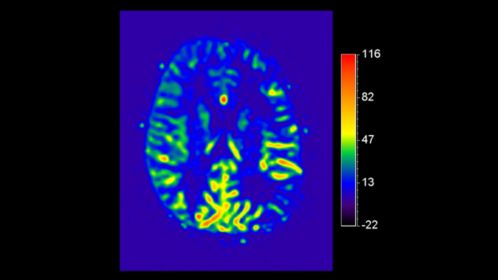

*pCASL (pseudo-Continuous Arterial Spin Labeling) ermöglicht die Darstellung der zerebralen Perfusion und funktionellen Physiologie auf kontrastfreie Weise mit geringer Verzerrung* und unter Abdeckung des gesamten Gehirns.